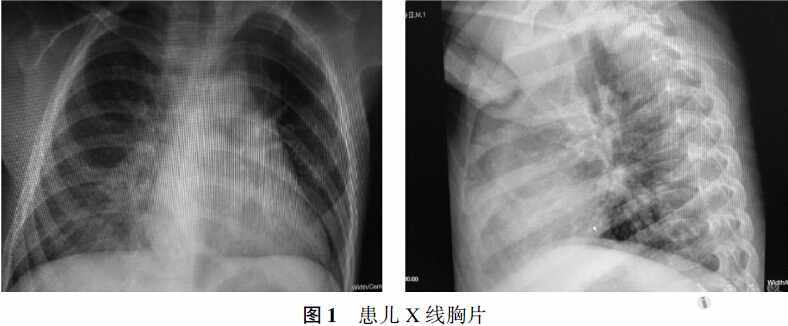

WBC 5.34×109/L,N 20.6%,L 69.9%,C反应蛋白11.50 mg/L (正常参考值0~8 mg/L)。血氧饱和度98%。尿、粪常规均正常。肝功及肾功均正常。心肌酶谱:乳酸脱氢酶300 U/L(正常参考值109~245 U/L),肌酸激酶同工酶29 U/L(正常参考值0~25 U/L),*丁酸羟**脱氢酶277 U/L (正常参考值72~182 U/L),提示心肌酶谱异常。葡萄糖4.30 mmol/L。抗“O”试验:1.20 IU/ml。X线胸片:右心缘旁纹理模糊、密集,见图1。